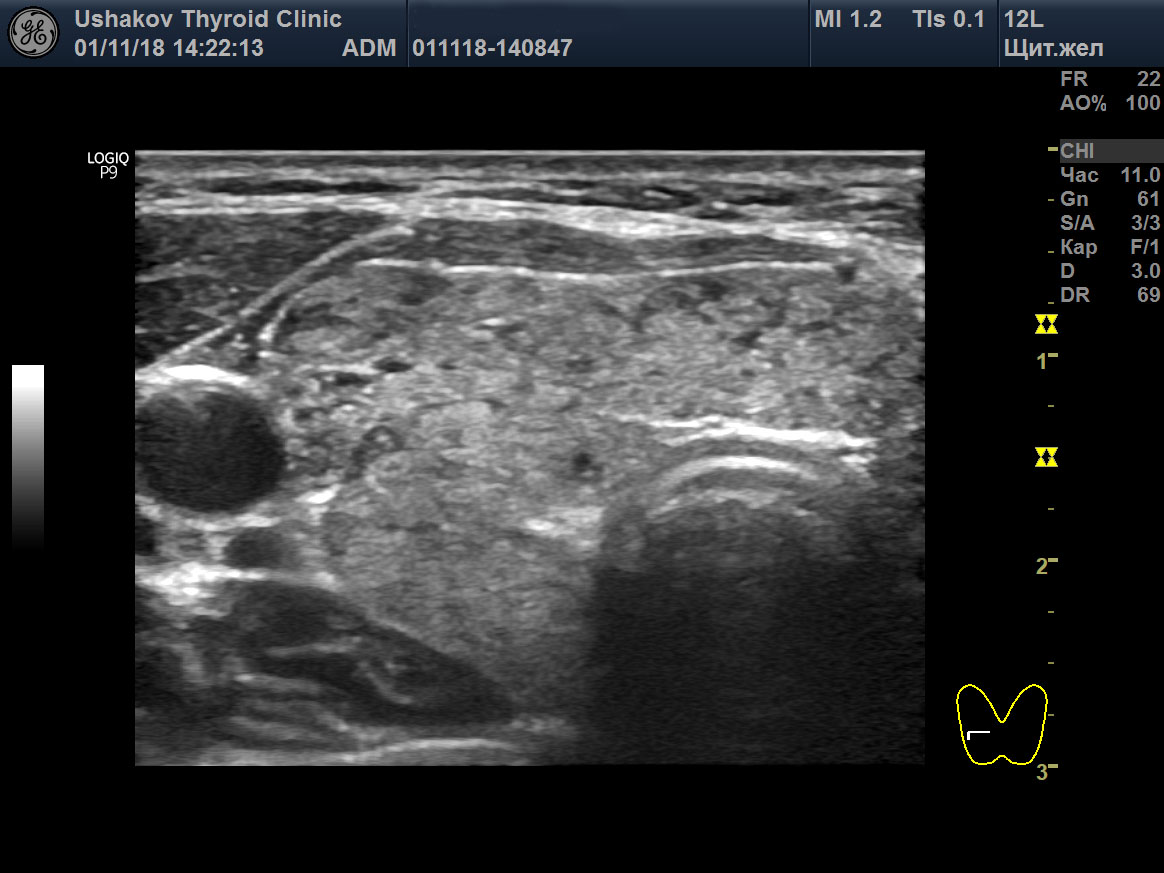

Рисунок 3 Правая доля ЩЖ пациентки 49 лет (поперечная и продольная проекции; В-режим). Преобладает фаза завершающейся регенерации. Большинство долек заполнено изоэхогенной (нормальной) тканью. Лишь по периметру определяются месяцеподобные гипоэхогенные элементы (остаточная лимфоидная ткань). Видны единичные дольки с активной фазой регенерации.